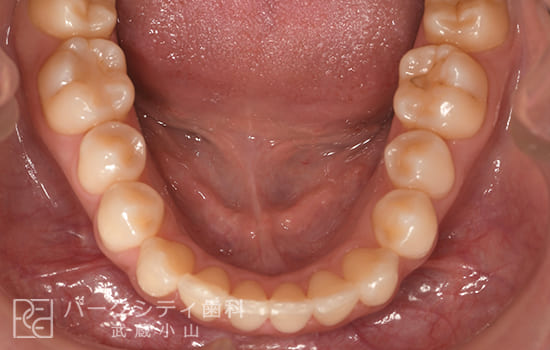

CASE.02

表側の部分矯正の症例

術前

術中1か月

術中3か月

4か月

- 主訴

- 前歯の隙間が気になる

- 治療法

- 表側の部分矯正

- 治療期間

- 4か月

- 費用

- ¥413,600

【内訳】

検査料:¥33,000

装置料:¥165,000×2(上下)

チェック:¥4,400×4

保定装置:¥16,500×2(上下)

上下表側に装置をつけ、隙間を閉じながら歯並びを整えて、約4か月で保定へ移行しました。